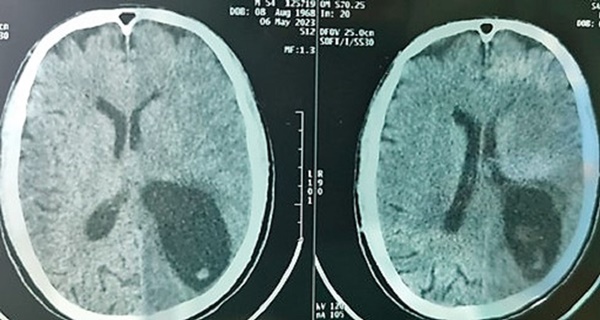

Hình ảnh chụp sọ não bệnh nhật S.V.T trước khi phẫu thuật. Ảnh: Bệnh viện cung cấp.

Bệnh nhân đã làm các xét nghiệm phân tìm ký sinh trùng (+), xét nghiệm Elisa chẩn đoán ấu trùng sán lợn Cysticercosis(+), chụp cắt lớp vi tính não cho thấy có nhiều ổ giảm tỷ trọng kèm phù não lớn vùng bán cầu trái.